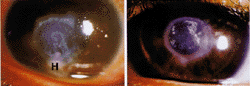

1例27岁男性为了矫正高度近视施行了无并发症的屈光角膜切除术,术后发生左眼角膜溃疡2天,患眼覆盖并用了角膜接触镜,局部应用硫酸磺胺甲氧苄啶多粘菌素B、氟米龙和氨丁三醇酮洛酸。术后1天,该角膜清亮,有轻微的前房反应,术后第2天,角膜渗出性前房积脓(图1,左),角膜培养有金黄色葡萄球菌生长,左眼角膜局部以环丙氟哌酸和头孢唑啉滴眼液每半小时点眼1次,用氢溴后马托品滴眼液每日2次,4天内前房积脓消失。在此后的2个月内溃疡慢慢愈合,中央部混浊部分变清。15个月后,右上睑形成一个霰粒肿,从该部位培养出了金黄色葡萄球菌,提示该患者为此微生物的带菌者。左眼小孔镜视力为20/100。环状中央部基质瘢痕伴有基质层变薄(图1,右)。4个月后,施行了穿透性角膜移植术,术后12个月植片保持透明。

图1 左图:术后2天,角膜中央治疗区可见一粗糙的溃疡性外观,伴有边缘明显加重的混浊和下方的前房积脓(H)。右图:9个月后,治疗区角膜持续性混浊,但无炎症表现